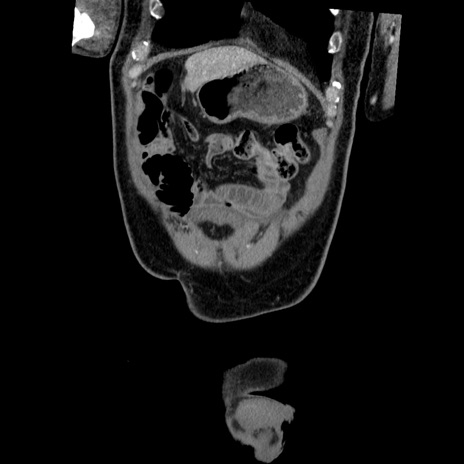

横断像

【症例】50歳代男性

【主訴】腹痛

【現病歴】AVMからの被殻出血のため回復期リハ病棟入院中。 本日午後3時頃急に下腹部痛が出現した。

【既往歴】AVM、被殻出血、虫垂炎、高血圧

【身体所見】意識晴明、左半身不全麻痺、会話の理解は良好、36.5°C、腹部:膨隆、全体に板状硬、下腹部正中に圧痛点あり、反跳痛-、筋性防御不明、右下腹部にope scar

【データ】WBC 9400、CRP 0.06